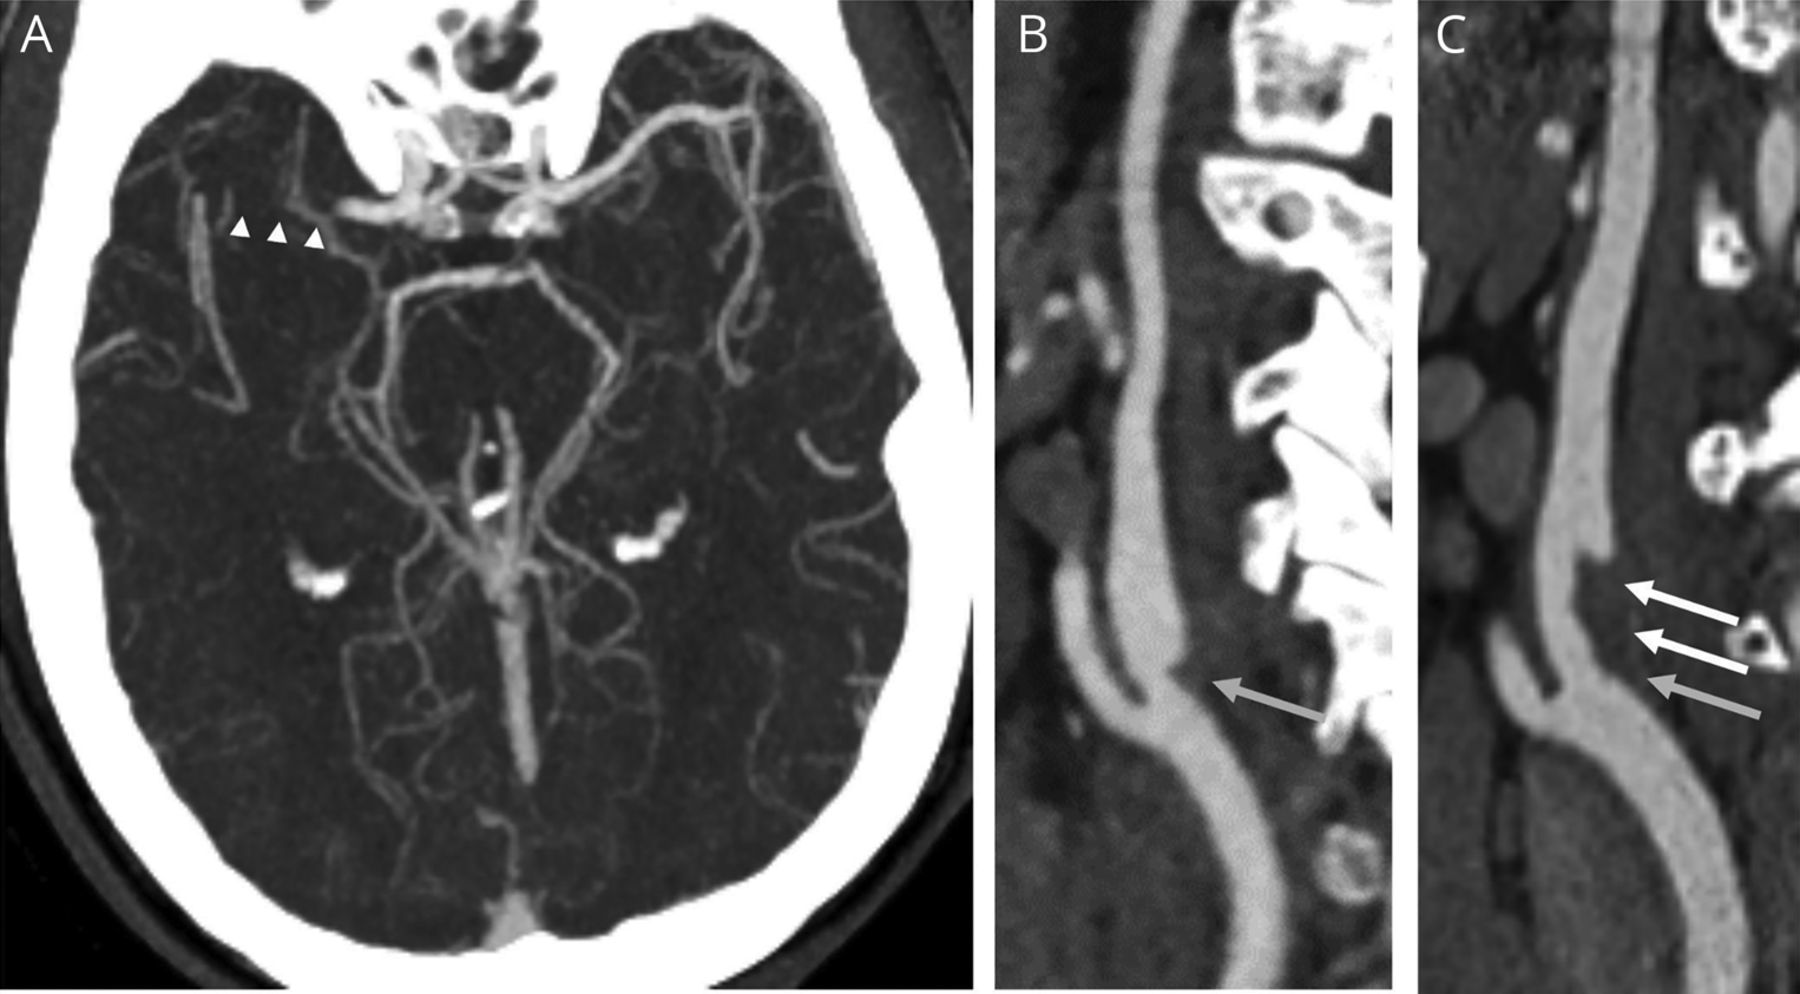

一个56岁的男人没有心血管疾病的风险因素出现急性右大脑中动脉中风(图,一个)通过静脉组织纤溶酶原激活物和血管内血栓切除术治疗。CT血管造影(CTA)显示一个三角形的充盈缺损后中的保证金的近端颈内动脉(ICA)与颈动脉web(地)一致,没有动脉粥样硬化(图B)。后续CTA显示进化2天内原位血栓,高高的覆盖(图中,C),之后抗凝就开始了。一个高高的杨树的线性充盈缺损ICA灯泡被认为代表一个内层的肌纤维发育不良的变体。1假设,血瘀,高高的下游表面可能会导致血栓形成和血栓栓塞中风。2

(一)CTA在演讲演示了一个正确的M1闭塞(箭头)。(B)矢状CTA在演讲演示了一个杨树充盈缺损后颈内动脉灯泡与颈动脉web(灰色箭头)一致。(C) CTA执行25小时后显示新的血栓沿着网络(白色箭头)。